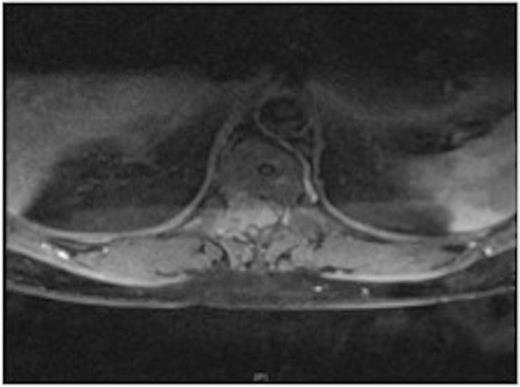

MRI showing the extra-dural tumour and extension into the soft tissue of the back

A one-year history of lower back pain, which was initially thought to be due to his liver metastasis, was investigated further with a full spine MRI scan. The scan revealed a large T10-11 extra-dural tumour with erosion of the T12 pedicle and extension into the soft tissue of the back. As a result of this discovery, the patient was referred for radiotherapy. Prior to commencement of this the oncologist requested a neurosurgical opinion from us.

MRI showing the T10-11 extra-dural tumour with erosion of the T12 pedicle